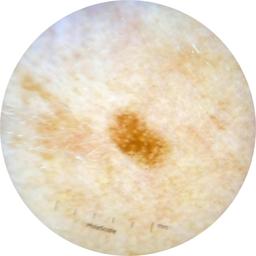

ISIC_2261268

2061 x 2061

Clinical

Field Value

acquisition_day 307

age_approx 50

anatom_site_1 Trunk

anatom_site_2 Posterior trunk

anatom_site_general posterior torso

concomitant_biopsy False

diagnosis_1 Benign

diagnosis_confirm_type single image expert consensus

family_hx_mm False

fitzpatrick_skin_type I

image_manipulation instrument only

image_type dermoscopic

lesion_id IL_8976478

patient_id IP_9156603

personal_hx_mm True

sex female